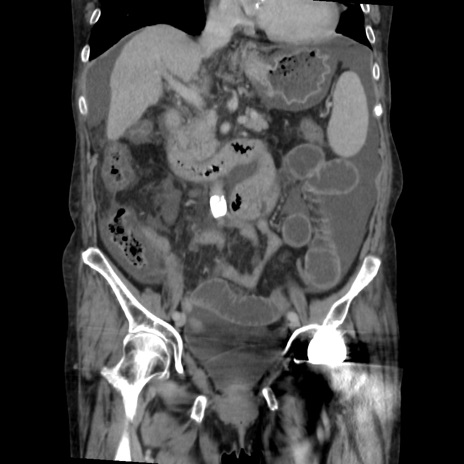

矢状断像

【症例】80歳代 女性

【主訴】腹部膨満感

【現病歴】他院にて肝硬変にてフォロー中。1週間前から便秘、腹部膨満感、臍部腫瘤あり受診となる。

【既往歴】肝硬変

【身体所見】腹部膨隆あり、皮膚変化なし、疼痛なし。

【データ】WBC 4600、CRP 0.25